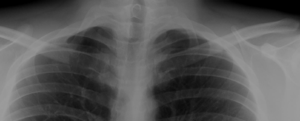

A cervical rib in humans is an extra rib which arises from the seventh cervical vertebra. Sometimes known as "neck ribs",[1] their presence is a congenital abnormality located above the normal first rib. A cervical rib is estimated to occur in 0.6% (1 in 150 people)[2] to 0.8%[3] of the population. People may have a cervical rib on the right, left or both sides.[4]

Most cases of cervical ribs are not clinically relevant and do not have symptoms; cervical ribs are generally discovered incidentally.[4][3] However, they vary widely in size and shape,[3] and in rare cases, they may cause problems such as contributing to thoracic outlet syndrome, because of pressure on the nerves that may be caused by the presence of the rib.[5]

On imaging, cervical ribs can be distinguished because their transverse processes are directed inferolaterally, whereas those of the adjacent thoracic spine are directed anterolaterally.[7]